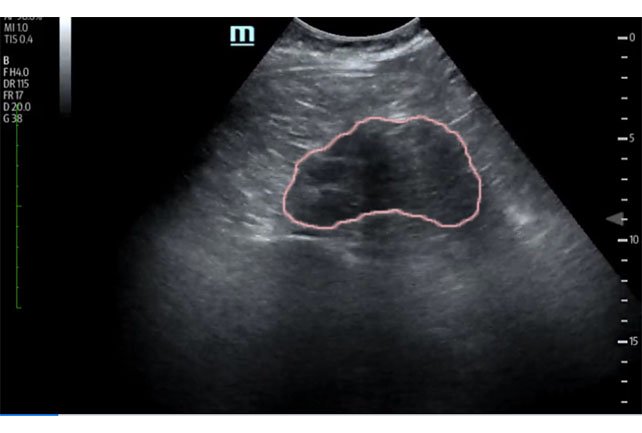

Bedside ultrasound was performed and demonstrated a hypoechoic area within the left kidney (images not shown). The non-contrast computed tomography (CT) of the abdomen and pelvis shows a significantly enlarged left kidney and a region of high-attenuation encapsulating the left kidney, concerning for acute hemorrhage.